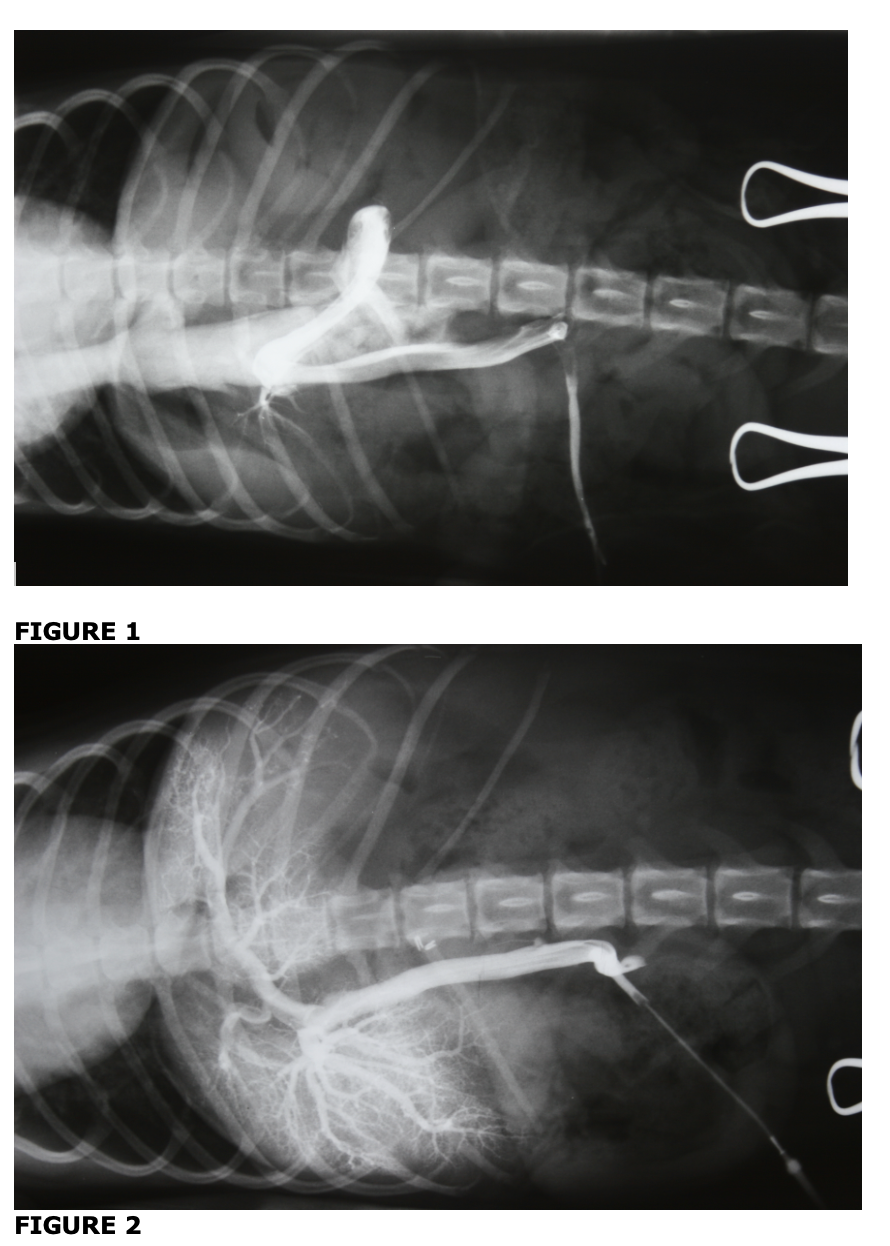

which image shows a normal hepatic portal vascular pattern. these images are from the same patient. what has changed from one image to another

image 2 = normal

in figure 2, clips have been applied to close the shunt and allow blood to flow into the liver

blood entering into vena cava and bypassing liver